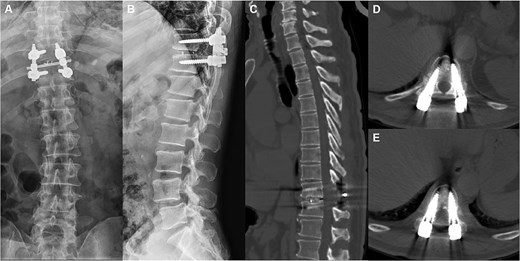

A 66-year-old male presented with a 1-year history of progressive low back pain and bilateral lower limb numbness, intensifying over the preceding month. Symptoms began insidiously without trauma and progressively worsened with prolonged standing and walking, improving with rest. The patient described deep, aching pain that significantly impacted his daily activities. Physical examination revealed bilateral lower limb numbness, especially prominent in the anterior thighs, an unsteady gait with a broad-based stance, decreased quadriceps muscle strength, reduced sensation below the navel extending to the groin, and positive bilateral Babinski signs indicating upper motor neuron involvement. Initial external X-rays suggested only L4 vertebral displacement, inconsistent with the clinical findings, prompting hospital admission for further evaluation. Refined imaging studies revealed previously unrecognized pathology. X-ray (Fig. 1A) and CT (Fig. 1B–D) demonstrated concomitant T10 vertebral body slippage, while MRI (Fig. 1E) showed severe T10/11 spinal cord compression with associated signal changes. The patient was diagnosed with thoracic spinal stenosis due to T10–T11 vertebral slip, explaining the bilateral lower extremity neurological symptoms and gait instability. Given the prolonged symptom duration, recurrent nature, and functional impact, surgical intervention was indicated after multidisciplinary discussion. The patient underwent T10–T11 thoracic interbody fusion with comprehensive decompression under general anesthesia. The procedure included herniated disc material removal, extensive posterior decompression, precise pedicle screw and titanium rod placement for stabilization, and autologous iliac crest bone grafting for interbody fusion. Postoperative management included comprehensive pain control and neurological monitoring. Follow-up X-ray (Fig. 2A and B) and CT (Fig. 2C–E) demonstrated successful vertebral realignment with the internal fixation in the ideal position. By postoperative Day 6, the patient reported significant back pain and leg numbness relief. Progressive improvement with structured physical therapy led to discharge on Day 10. One-year follow-up examination (Fig. 3) revealed stable fixation with continued symptom resolution, enabling free ambulation and complete return to normal activities.

Postoperative X-ray and CT showed that the slipped thoracic 10 vertebra was reset, the internal fixation device was ideally positioned, and the spinal cord compression had disappeared.